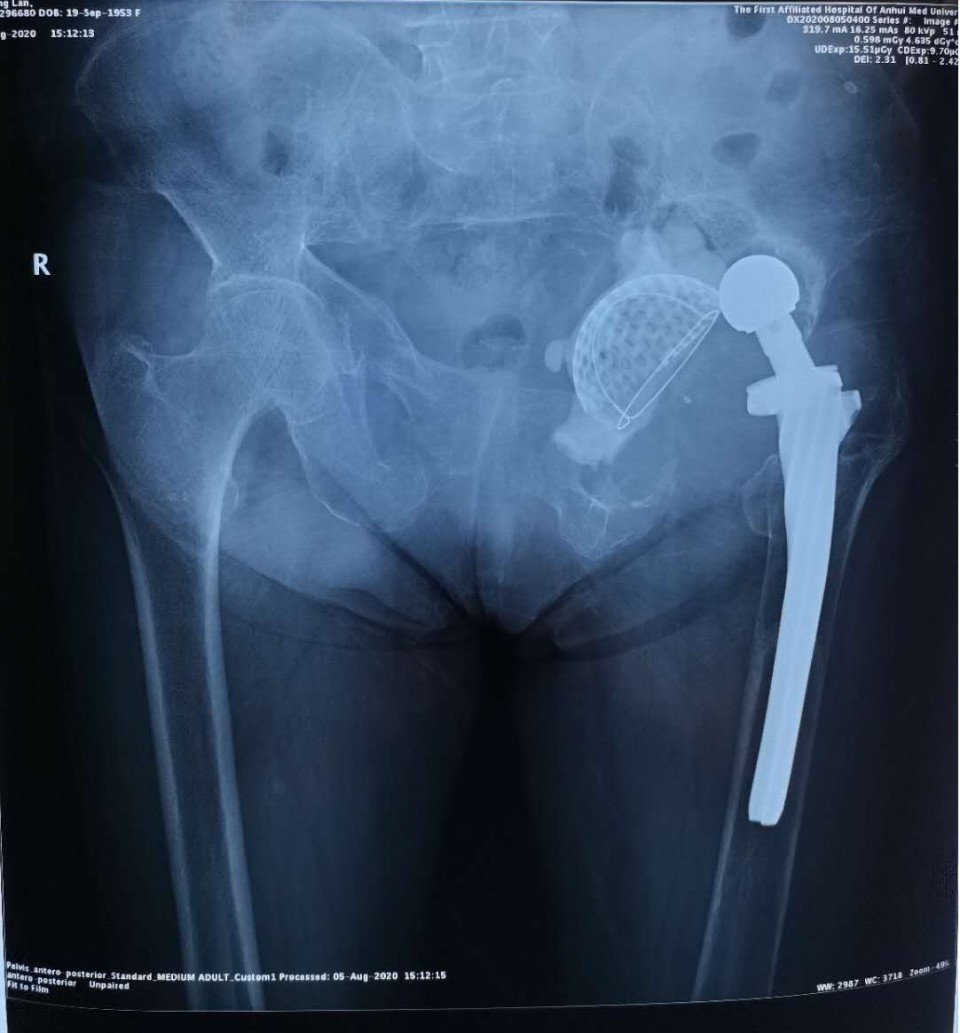

患者,瞿某某,女性,72岁。因“左侧髋关节疼痛伴活动受限1年”入院。该患者2006年因为股骨颈骨折在当地医院接受全髋关节置换手术。2016年因植入的假体无菌性松动接受了翻修手术。去年左侧髋关节再次出现疼痛,今年4月份症状明显加重,在当地医院摄片检查,发现假体再次松动。为求进一步诊治来到我院。

患者入院后经过详细的检查和评估后发现,因左侧髋关节接受过两次手术,原有的骨盆结构已经面目全非,存在巨大的骨缺损,利用常规的人工关节假体进行修复重建十分困难。关节外科团队在尹宗生教授的带领下为患者施行了翻修手术。利用3D打印技术联合国内的厂家进行技术研发,个性化地为患者量身设计了生物锁和髋臼假体。

手术过程中发现髋关节周围存在大量的原假体磨损碎屑,原髋关节处于脱位状态。髋臼假体连同原先的骨水泥均已经松动,股骨侧假体也松动了。当把原先所有的假体取出后,呈现在术野中的是一个直接通向盆腔的巨大窟窿。如果采用常规的髋关节置换假体是不可能填补如此巨大的骨缺损的。手术当中尹宗生教授仔细分离骨盆周围的重要结构,之后将预先打印好的髋臼假体安装在残缺不全的骨盆上,该假体正好能够匹配骨缺损。在预先设计预留的钉孔上置钉,并在髋臼底部植入了人工骨。手术共耗时3小时,术后患者康复满意,没有出现并发症,已顺利出院。